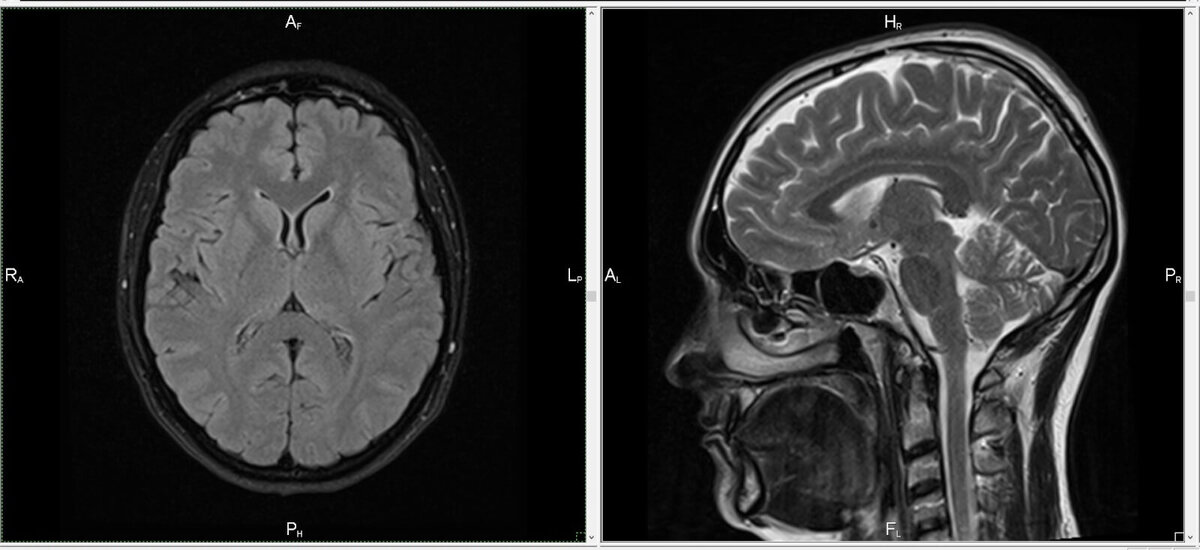

При депрессии сильно страдают три зоны мозга, отвечающие за обработку и регулирование наших эмоций: амигдала, гиппокамп, префронтальная кора. При депрессии ведущими эмоциями становятся тревога и страх, что приводит человека к постоянному напряжению, и невозможности “переключиться”.

При депрессии объем гиппокампа снижается, изменяется структура амигдалы и префронтальной коры. Нарушается “серотониновый” обмен, гиппокамп перестает воспроизводить новые нейроны, снижается нейропластичность. Такое нарушение при депрессии, без необходимого лечения, приводит к ощущению беспомощности и тотальной подавленности.